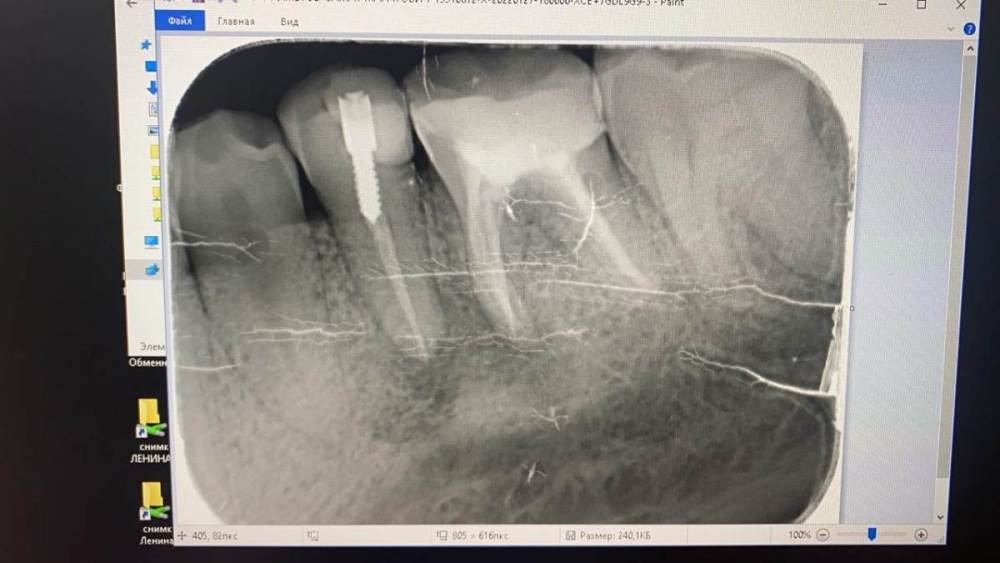

Ахметов самат Опубликовано 27 января, 2022 Поделиться Опубликовано 27 января, 2022 (изменено) От какого зуба гранулематозное воспаление? От 36 или 35? 36 зуб лечили 8 лет назад, 35 лечили год назад Заранее буду благодарен Изменено 27 января, 2022 пользователем Ахметов самат Ссылка на комментарий

red_butler Опубликовано 27 января, 2022 Поделиться Опубликовано 27 января, 2022 качество снимка не позволяет его интерпретировать, сделайте Кт 1 Ссылка на комментарий